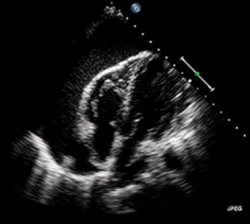

| A 2D echo transthoracic echocardiogram of pericardial effusion. The "swinging" heart. | |

ECG: may present with sinus tachycardia, low voltage QRS as well as electrical alternans.[2] Due to the fluid accumulation around the heart, the heart is further away from the chest leads, which leads to the low voltage QRS. Electrical alternans signifies the up-and-down change of the QRS amplitude with every beat due to the heart swinging in the fluid (as displayed in the ultrasound image in the introduction) .[1] These three findings together should raise suspicion for impending hemodynamic instability associated with cardiac tamponade.

Echocardiogram (ultrasound): when pericardial effusion is suspected, echocardiography usually confirms the diagnosis and allows assessment of the size, location and signs of hemodynamic instability.[4] A transthoracic echocardiogram (TTE) is usually sufficient to evaluate pericardial effusion and it may also help distinguish pericardial effusion from pleural effusion and MI. Most pericardial effusions appear as an anechoic area (black or without an echo) between the visceral and the parietal membrane.[1] Complex or malignant effusions are more heterogeneous in appearance, meaning they may have variations in echo on ultrasound.[5] TTE can also differentiate pericardial effusion based on the size. Although it's difficult to define size classifications because they vary with institutions, most commonly they are as follows: small <10, moderate 10–20, large >20.[5] An echocardiogram is urgently needed for evaluation when there is concern for hemodynamic compromise, a rapidly developing effusion or history of recent cardiac surgery/procedures.[1]

A large anechoic (black) pericardial effusion as seen on ultrasound. Closed arrow: the heart, open arrow: the effusion -